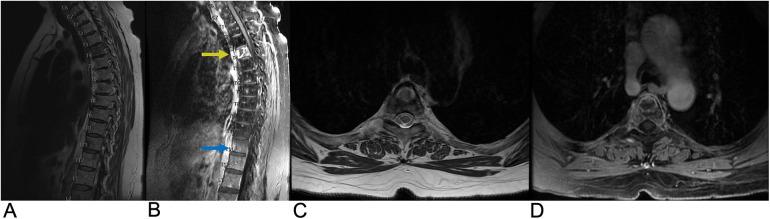

Spinal lesions encompass a diverse range of pathologies, including primary and secondary tumors, infectious processes, vascular malformations, traumatic injuries, and degenerative conditions, each with distinct imaging characteristics crucial for accurate diagnosis and management. Imaging plays vital roles in assessing lesion morphology, anatomical localization, and neurological impact, guiding clinical decision-making and therapeutic planning. This review systematically explores spinal lesions based on their anatomical compartments, highlighting key radiological features and providing a comprehensive reference for radiologists.